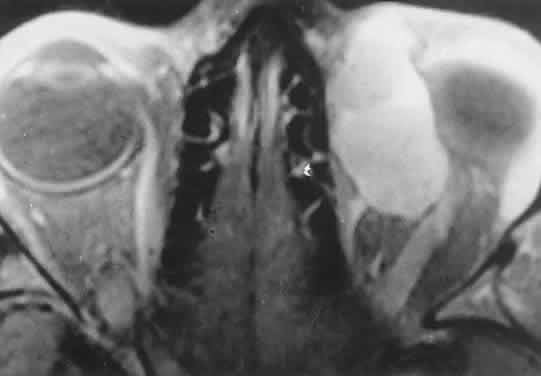

Orbital myositis may represent a greater proportion of cases of IIPT in childhood than in adulthood, and involvement of multiple extraocular muscles may occur more frequently in children than inadults. In orbital myositis, early diplopia and increased discomfort with attempted eye movement are typical symptoms. CT may show enlargement of one or more extraocular muscles in one or both orbits (Figs. 21 and 22). When a single muscle is involved, the specter of a primary or metastatic neoplasm within the muscle may be raised. However, external inflammatory signs, considerable pain and limited motility, and an explosive onset of symptoms within 24 hours all suggest orbital myositis. The uniform enlargement of the muscle, including its tendinous insertion (see Fig. 22), also helps distinguish the process from a neoplasm, which might be expected to produce a more focal, globular expansion. Echography may support the diagnosis of inflammation by showing edema in the episcleral space as a relative sonolucency between the scleral and orbital fat echoes (Fig. 23). Its CT counterpart is an increase in the radiodensity and thickness of the ocular tunica.

Fig. 21. A. This 16-year-old boy had acute onset of bilateral proptosis, pain, diplopia, chemosis, and conjunctival injection. B. Bilateral enlargement of the superior and medial rectus and inferior oblique muscles. Other sections showed similar involvement of other extraocular muscles.

Fig. 22. The uniform enlargement of the left medial rectus muscle, including its tendinous insertion, is characteristic of orbital myositis.